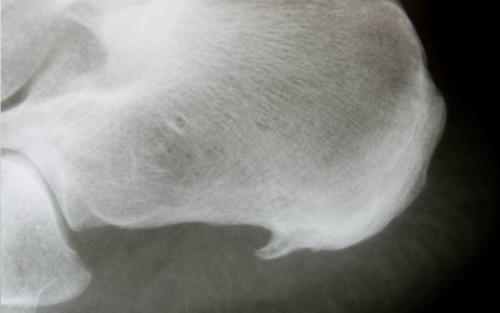

درمان خار استخوانی

05 آذر 1402

4341 مشاهده

بیشتر بخوانید